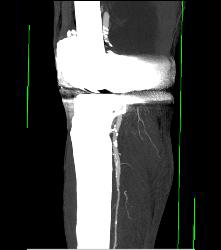

Bakers Cyst